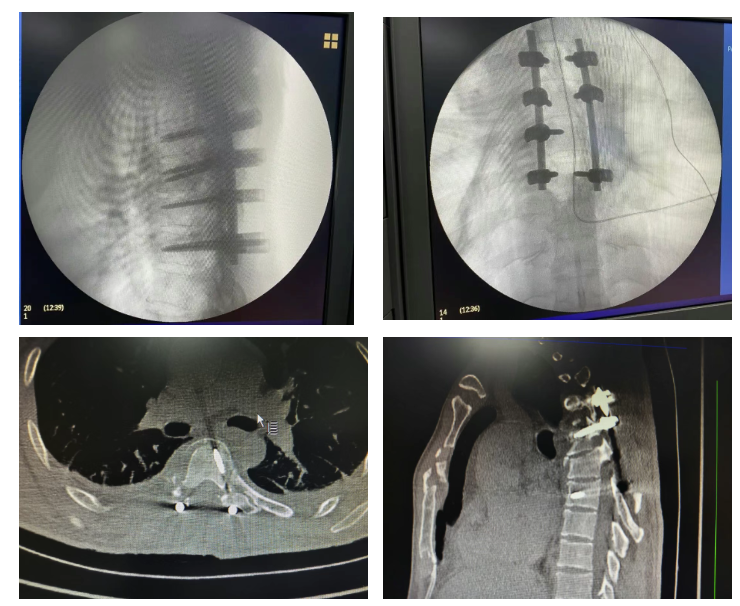

手术中,医护团队默契配合,精准实施胸椎骨折切开复位内固定术 + 椎管减压术(T4-7),手术最终顺利完成。术后即时评估显示,患者下肢麻木、疼痛症状较术前有明显改善,下肢肌力也出现初步恢复迹象,为后续康复奠定了良好开端。